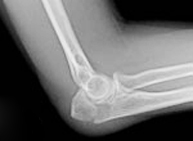

Fracturas de cabeza de radio

Las fracturas de radio son producidas fundamentalmente de forma indirecta por transmisión de un impacto de la mano hacia el codo. Pueden ser caídas fortuitas o durante la realización de actividad deportiva o laboral. Cuando tienen lugar el codo se inflama y su movimiento es muy doloroso. El tratamiento busca la restitución de la anatomía normal del radio para iniciar el movimiento cuanto antes e impedir la aparición de rigidez.